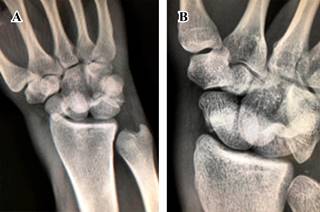

Masculino de 23 años de edad, sano, quien sufre caída del propio plano de sustentación contundiendo mano derecha con mecanismo de hiperflexión. Inicia con dolor, limitación funcional y edema importante en muñeca, motivo por el cual acude al servicio de urgencias. A la exploración física, llama la atención edema y deformidad en dorso de muñeca derecha con limitación funcional a expensas del dolor, sin alteraciones neurovasculares distales. Se realizan radiografías en proyecciones anteroposterior y oblicua de mano (Figura 1); se observa incongruencia entre líneas carpales con sospecha de fractura de escafoides. Se realiza tomografía computarizada (Figura 2), con la cual se completa diagnóstico de fractura luxación transescafo-perilunar.

Figura 1: Radiografías (A) anteroposterior y (B) oblicua de muñeca derecha. Se demuestra pérdida de las líneas de Gilula y fractura en escafoides.